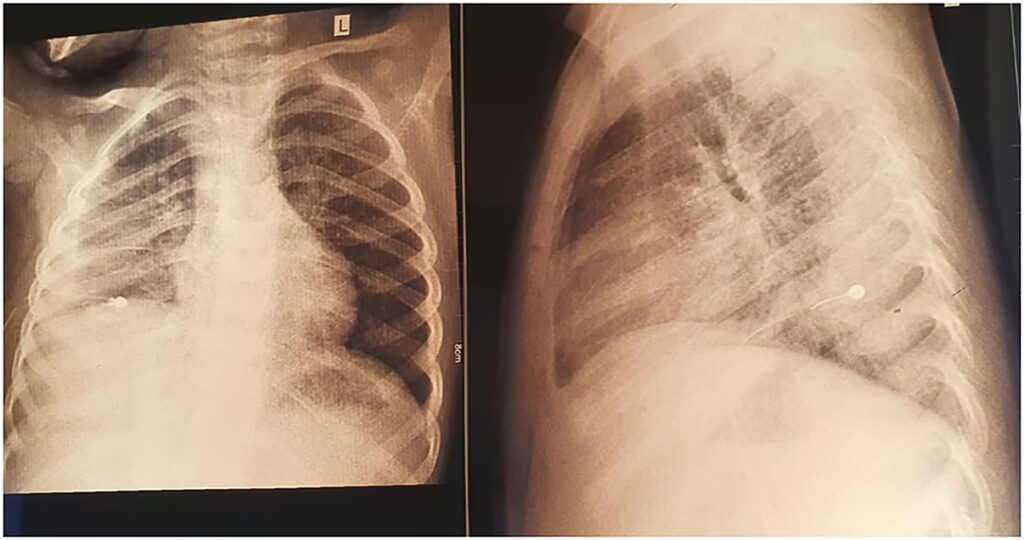

At diagnosticere en Chlamydia pneumoniae-infektion kan være en udfordring. En læge kan have mistanke baseret på symptombilledet, især hvis en patient ikke reagerer på standard penicillin-behandling. Røntgenbilleder af lungerne kan vise tegn på lungebetændelse, men fundene er ofte diffuse og ikke specifikke for denne bakterie.

| Røntgen af lunger | Velafgrænset fortætning i en lungelap | Diffus og pletvis fortætning |